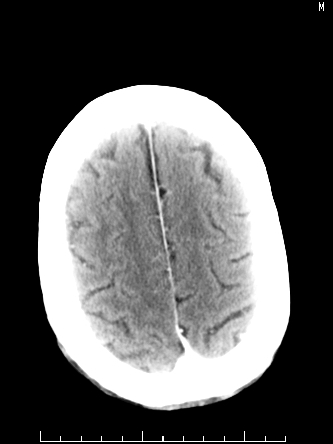

m/50,头昏头痛1月,近3天感觉左半肢体活动不利,自述半年前呈患肺tb,腰穿脑脊液未见特殊改变。现做头颅ct请大家会诊。

ct值?是囊变?梗塞软化灶形成

考虑颅内感染性病变:结核可能性大。

结核性脑膜炎,结核瘤,梗塞灶三症并存,提示颅内结核感染可能性大。

感染性病变;脑干脓肿(脓肿壁形成期),基底节及内囊(脑炎期)。顺便问一句,该病人是不是抵抗力很差,有没有糖尿病。

右侧基底节区缺血性脑梗塞.脑干区考虑结核.

可考虑结核,患者水肿范围大,囊性病灶边缘密度较高,不考虑胶质母细胞瘤